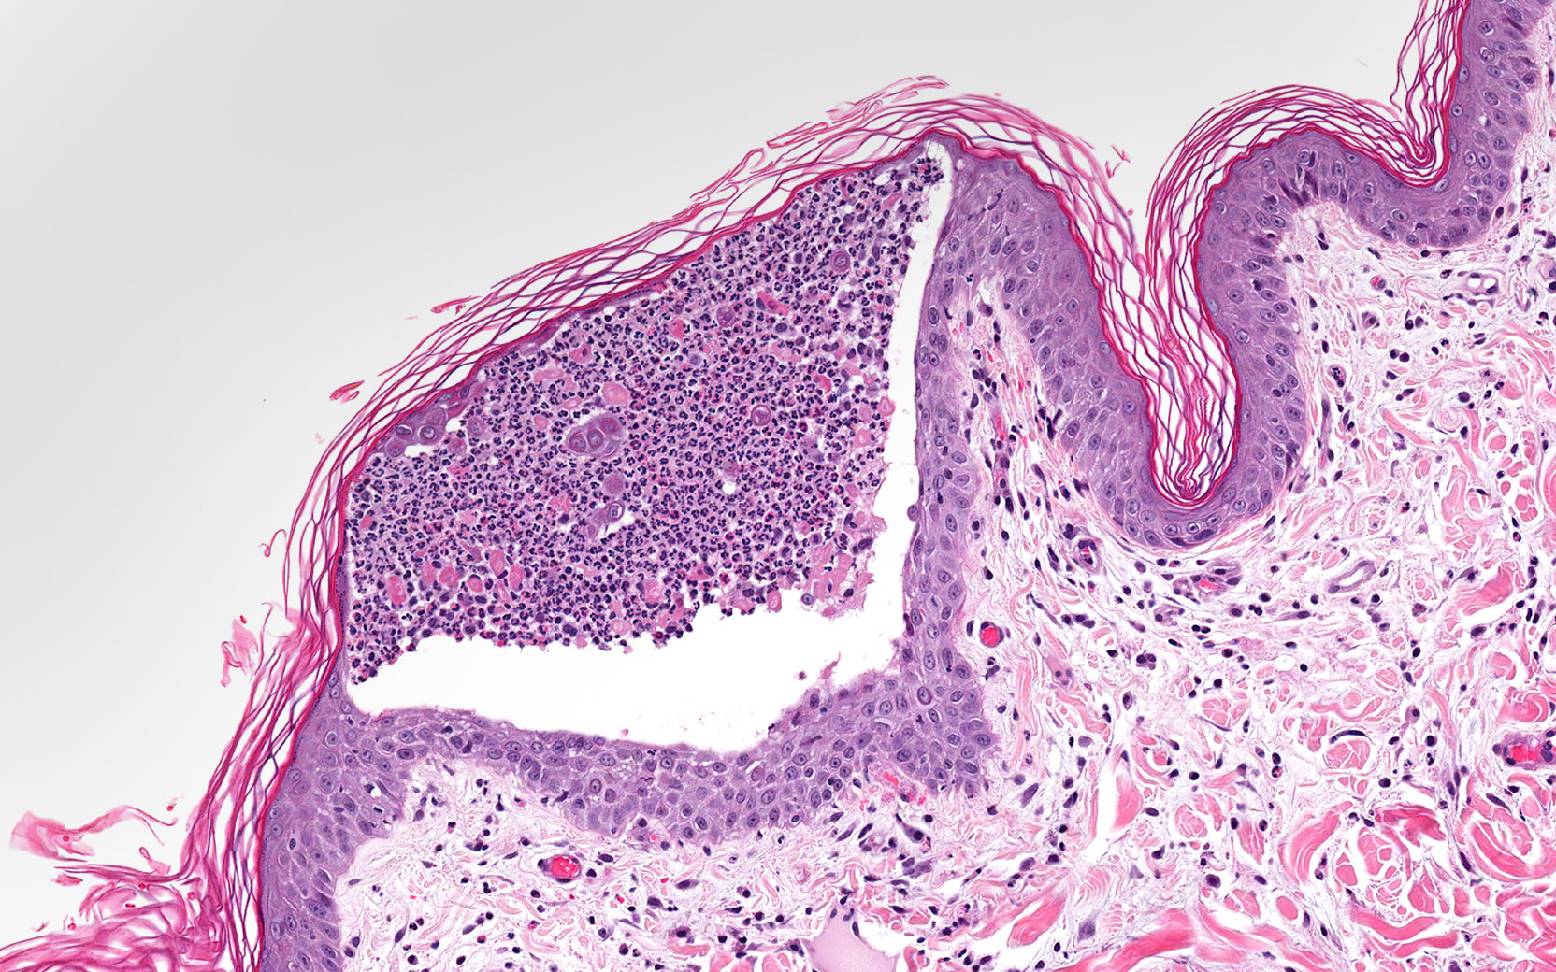

In the group of pemphigus diseases, the body produces immune cells that attack specific proteins that bind skin cells together. Pemphigus foliaceus is the most common form of pemphigus in dogs.

The destruction of these cellular connections leads to the formation of large pustules in the skin, which become inflamed. As the condition progresses, this causes the outermost layers of the skin to detach and die off. Extensive open skin wounds form, which heal poorly and are prone to infection. Symptoms are most commonly seen on the nose, bridge of the nose, around the eyes, ears, and paws, usually appearing as scabs, scales, or redness. In severe cases, fever and loss of appetite may also occur.

The characteristic clinical presentation allows your veterinarian to make an initial presumptive diagnosis. A biopsy (examination of a tissue sample) or the examination of cellular material from an opened pustule, combined with a blood sample, provides confirmation and thus confirms the diagnosis.